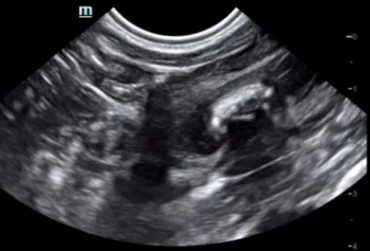

Ciało obce w pęcherzu moczowym jako jądro krystalizacji dla kamienia moczowego – opis przypadku

Zapalenie pęcherza moczowego jest częstą dolegliwością spotykaną w gabinecie lekarza weterynarii. Brak lub nieodpowiednia diagnostyka i leczenie chorób dróg moczowych u psów oraz kotów może prowadzić do groźnych powikłań oraz niepotrzebnie narażać zwierzę na cierpienie. W artykule opisano przypadek kota rasy europejskiej, który został postrzelony ok. 4 lata temu z broni pneumatycznej. Pocisk ze śrutu utkwił w pęcherzu moczowym zwierzęcia oraz stał się jądrem krystalizacji dla kamienia moczowego. W tekście zostały opisane teorie dotyczące tworzenia się kamieni moczowych, metody diagnostyki oraz leczenia kamicy pęcherza moczowego i krystalurii.